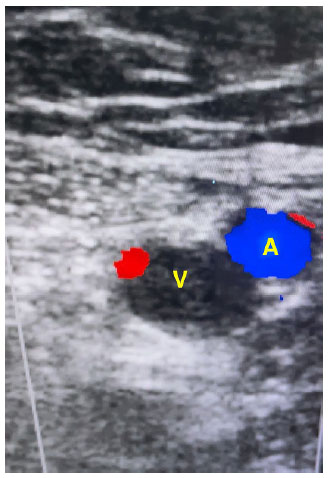

Com auxílio de aparelho de Ultrassonografia portátil, decidi por fazer uma varredura nos principais vasos cervicais e de membros inferiores, pois havia necessidade de troca de cateter para prosseguir com as sessões de hemodiálise da paciente. No caso da paciente, havia o relato de dificuldade de punções anteriores, além de dor e edema em membro inferior direito e sangramento no orifício de punção associado a baixo fluxo no cateter da veia jugular interna esquerda. Inicialmente, avaliei os vasos inguinofemorais da paciente. À esquerda, em todo o trajeto para possíveis punções, a artéria estava por cima da veia, o que dificultaria sua punção “às cegas”. Veias femorais comum e superficial e veia poplítea esquerdas apresentavam bom fluxo ao doppler em cores e com boa compressibilidade, não denotando sinais de trombos na região. Ao avaliar os vasos inguinofemorais à direita, local de tentativas prévias de punção vascular, foi evidenciado que o lúmen venoso apresentava conteúdo heterogêneo, hiperecoico, além de fluxo prejudicado visualizado no doppler em cores, denotando sinais de trombose venosa naquele sítio.